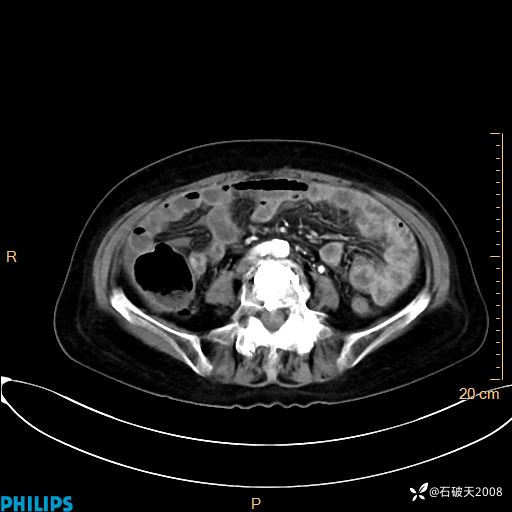

平扫